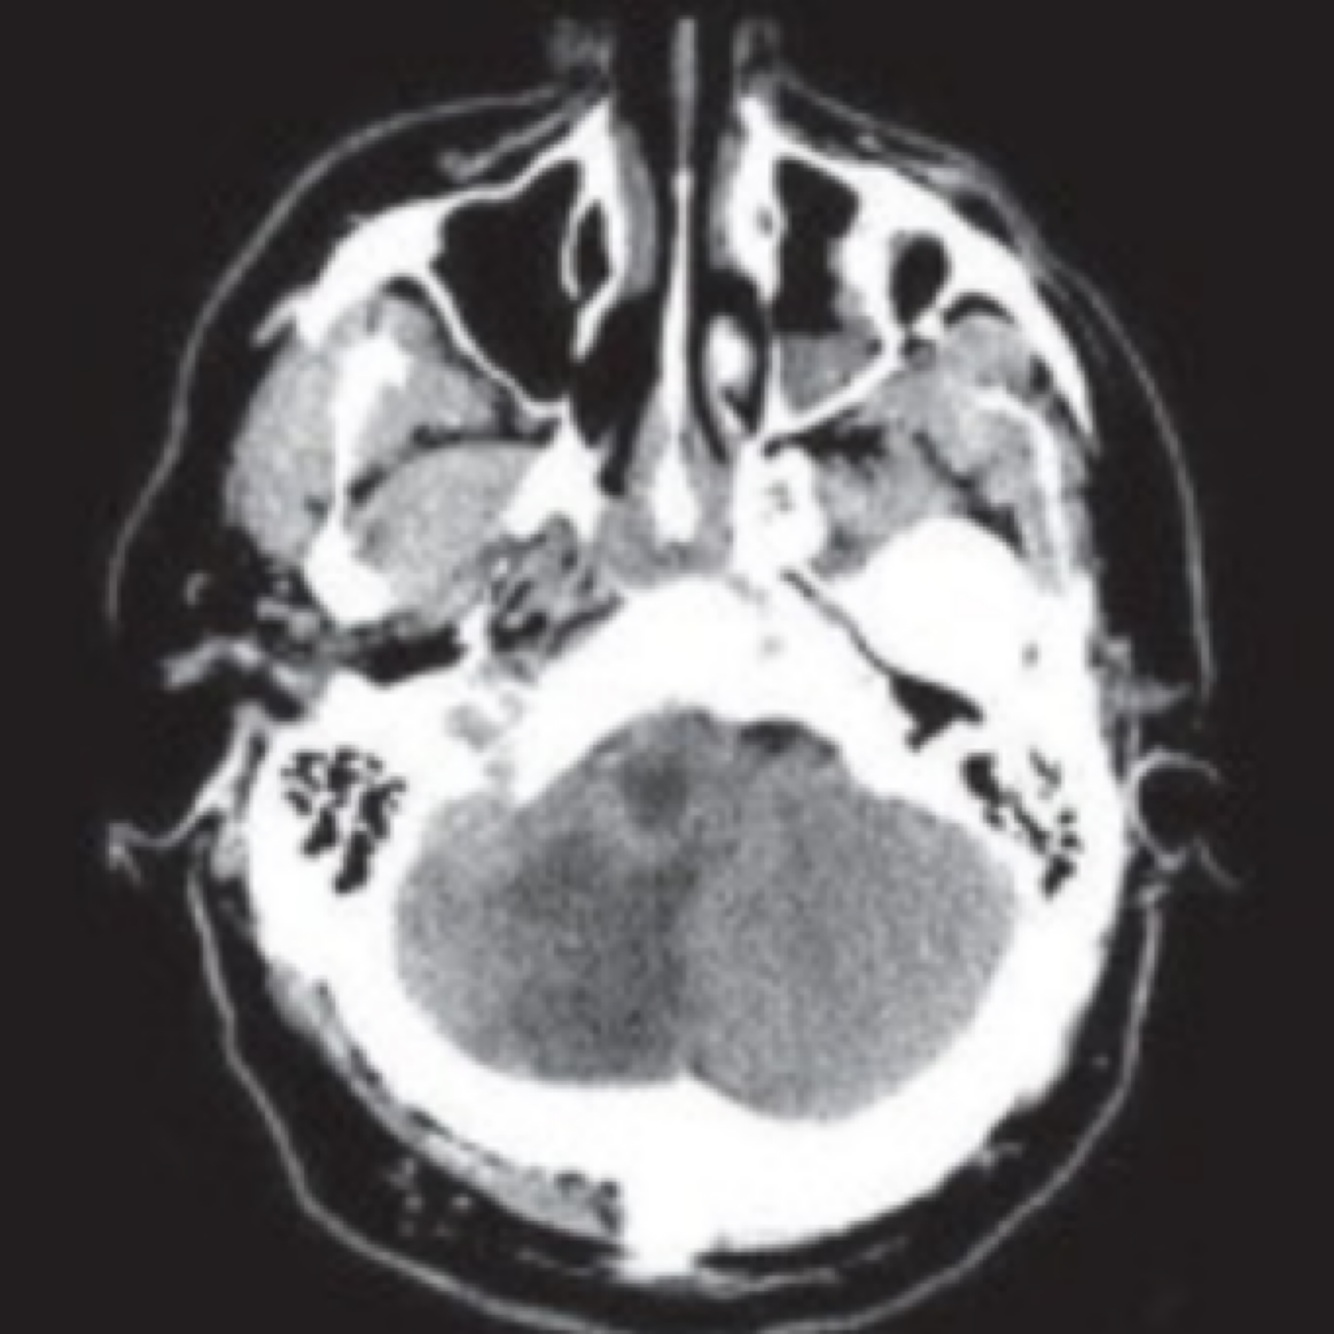

Que arteria se encuentra afectada

PICA